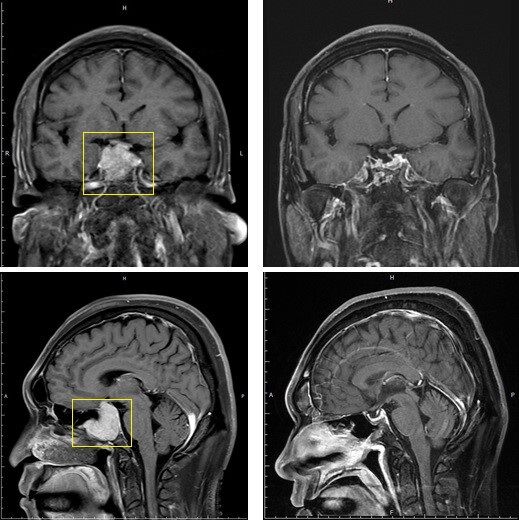

▲病人術前術後對照圖,黃框處為術前腫瘤位置,術後(右側)腫瘤已消失。(圖/北醫附醫提供)

經耳鼻喉科檢查後,於男子鼻腔深部蝶竇處發現息肉樣腫塊,核磁共振(MRI)檢查確認為顱底大型腦下垂體腫瘤(pituitary tumor),腫瘤直徑超過2.5公分,並向顱內上方生長,壓迫視神經及鄰近腦部結構,導致頭暈、頭痛等多項神經學症狀。

陳淑美指出,病人術後恢復良好,定期追蹤一年後,核磁共振檢查顯示腫瘤完全消失,無復發跡象,順利重返職場。另外,術後病人也恢復原本溫和開朗的個性,家屬直呼此次手術,不只成功切除腫瘤也改善了家庭關係。